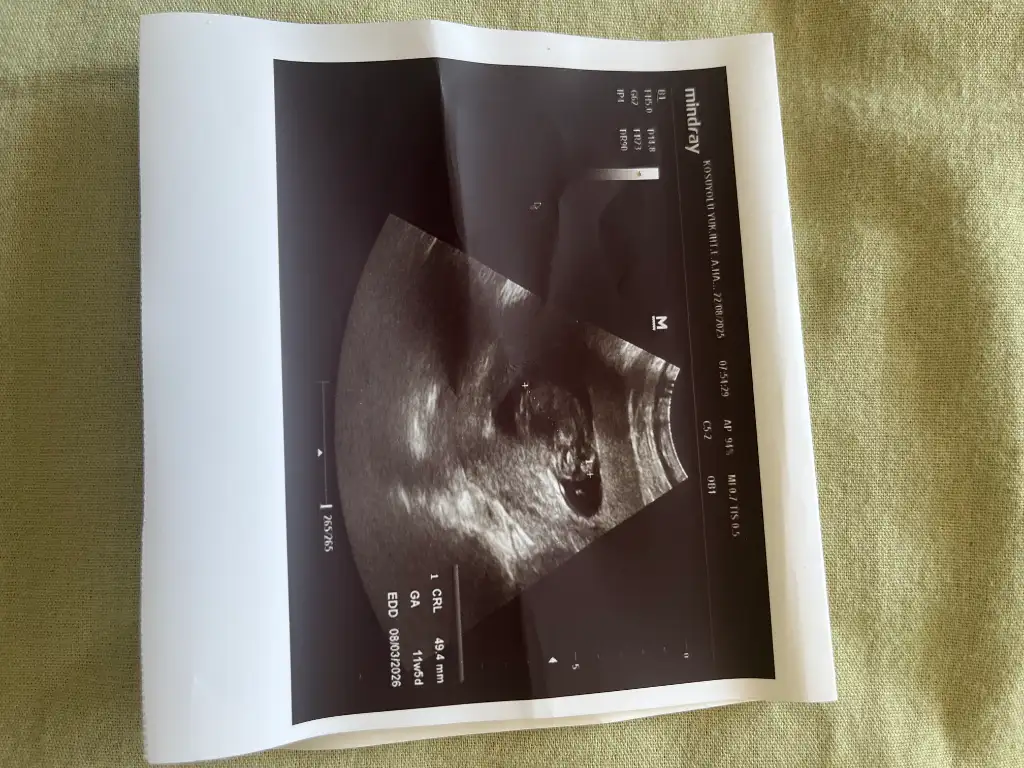

Benim nedir sizce 12+1Erkek bence

MerhabalarBenim nedir sizce 12+1

Doktor cinsiyyet tahmininde bulunmadi mi acaba? Cunki 12+1 . Genelde soylemeyince bu haftalarda kiz geliyor. Erkegi hemen gore biliyorlarmis

13. haftadan sonraki bir ultrason fotoğrafı varsa chatgptye sorun bence nub teorisine göre benimkini ve arkadaşımın bebeğini doğru tahmin ettiBenim nedir sizce 12+1